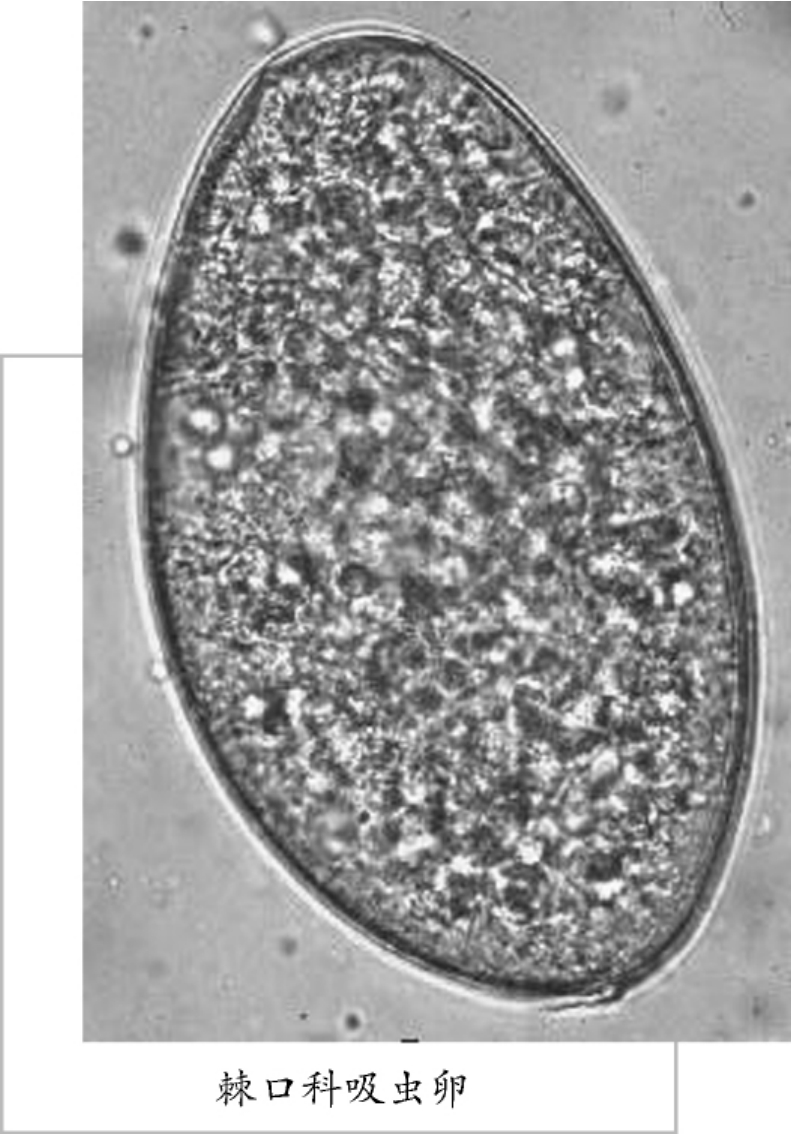

棘口科吸虫

棘口科吸虫种类繁多,全世界已报道的有600多种。露珠主要是鸟禽类,其次是哺乳类,少数寄生于鱼类。有的棘口吸虫可在多种动物宿主寄生。寄生于人体的棘口吸虫主要分布于东南亚地区,我国已报告的可在人体寄生的棘口吸虫有10种,其中日本棘隙吸虫在福建和广东局部地区有流行。藐小棘隙吸虫在安徽局部地区的人群感染率达13.71%。

棘口科吸虫虫体长形,体表有棘、口、腹吸盘相距甚近,口吸盘周围有环口圈或头冠,环口圈或头冠之上有1个或2圈头棘。睾丸2个,前后排列在虫体的后半部。卵巢位于睾丸之前。卵大,椭圆性,壳薄有卵盖。成虫寄生于肠道,偶尔也可侵入胆管。

棘口科吸虫成虫多寄生于小肠上段,以头部插入黏膜,引起局部炎症,病人可出新腹痛、腹泻、或其他胃肠道症状,严重感染者可有厌食、下肢浮肿、贫血、消瘦、发育不良甚至死亡。